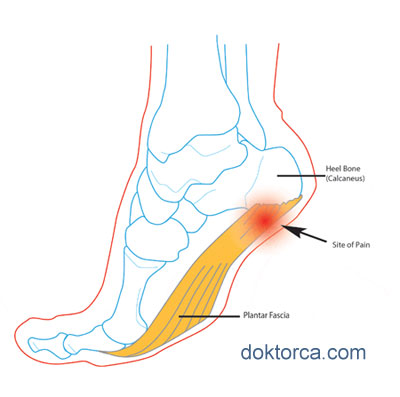

Topuk dikenleri çoğu zaman ağrısız sızısız olsa da bazen çok ciddi ve dayanılamaz ağrılara neden olabilir. Bu ağrıların nedeni aslında topuktaki dikene eşlik eden ve topuk kemiğini (heel) ayak tabanına bağlayan zarın ve bağdokusunun iltihaplanmasından kaynaklanır (plantar fasciitis)

- ayak tabanı bağdokusunun gerilmesi (plantar fascia),

Topuk Dikenleri genelde ağrısızdır. Dikene bağlı bölgede oluşan yumuşak doku iltihabı ve bağdokusunda tekrarlayan yırtılma ve gerilmeye bağlı ara ara kronik ve giderek artış gösteren ağrılar oluşabilir. Bu ağrılar genelde sabahların erken saatinde hatta ilk yataktan kalkıp ayak üstüne durulduğında hissedilir.

Bu durumu yaşayanlar topuk kısmına adeta bir bıçak veya çivi saplanır gibi bir ağrı olduğunu anlatır. Günün ilerleyen saatlerinde bu ağrılar hafifler ve tatsız tarifi zor müphem bir sızı devam eder. İlerleyen vakalarda ise yürüme bozukluğuna bile neden olabilecek ağrılar meydana gelebilir.